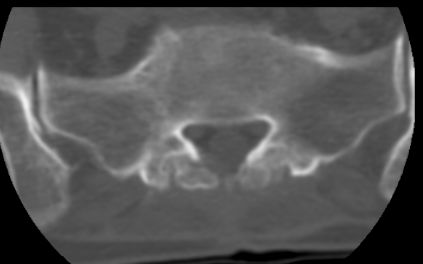

以下是引用余辉在2007-9-4 21:00:00的发言:[br]椎体棘突有点异常(像是被切割了),不知有否手术史,如椎体融合术等。单纯的退行性变可以出现椎间隙变窄,但同时一般会出现椎体上下缘的硬化增生,且椎体间完全融合的机率更小,本例椎体完全融合且椎体上下皮质缘破坏掉了,如果没有手术史,就应该考虑椎间盘炎性病变了,且椎体棘突及棘间韧带的变化也并不是不支持这个,多数小关节也融合了,且其形态也容易让人联想到如强脊炎及类风关等病变。[br][br][本贴已被 余辉 于 2007-9-4 21:03:55 修改过]

以下是引用chry3在2007-9-4 20:42:00的发言:[br]椎间盘病史?是什么样的病史,无双下肢放射痛,那就不是椎间盘突出了。是感染、什么性质的?[br]从图象看椎间隙消失,椎间盘组织未见,锥体滑脱是因为椎间盘溶解造成的[br]l4、5椎体骨质结构未见异常,l5上缘是l4的长期压迫所致[br]还是考虑椎间盘感染,结核。[br]